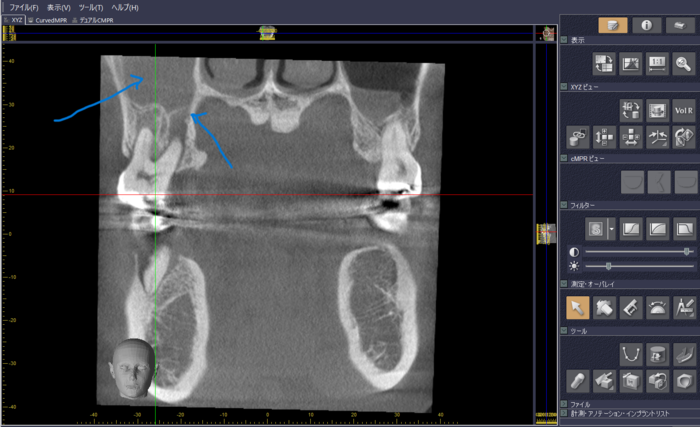

図2は、矢印が左右の上顎洞(副鼻腔の一つ)を示していますが、左側は白くなっています。炎症がないものは右側のように黒く見えるのですが、炎症があると白く見えます。果たしてこの炎症はどこから来ているのか探ってみると、右上の一番奥の歯の神経が死んでしまって、それが原因で右側の上顎洞が炎症を起こしています。図3では、矢印の部分が上顎同に通じているように見えます。このように鼻の病気でも歯が原因の場合も考えられるので、CT撮影は有効な診断基準になります。

上 図2:下 図3